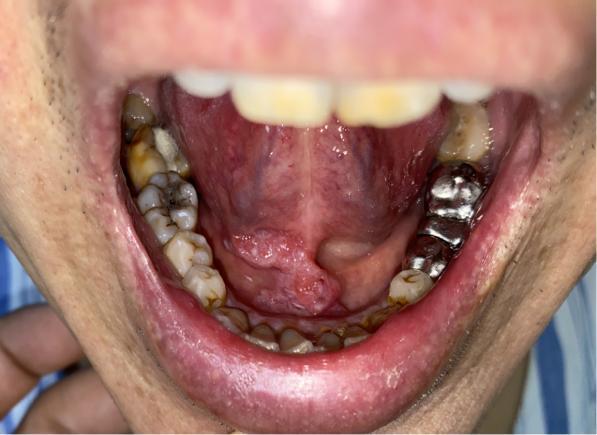

口腔红斑是什么样子的

口腔红斑是什么样子的,口腔红斑图

口腔红斑

(1)口腔黏膜出现的白斑,红斑,黏膜下纤维性变,属于癌前病变.

迎春节送健康丨哈医大一院口腔专家提示别小看口腔溃烂要小心口腔癌

口腔红斑图

口腔癌红斑图片

口腔红斑初期症状图片

早期口腔红斑图片

口腔红斑图片

口腔内疣状增生图片

口腔疣体图片早期

口腔初期小疣体图片